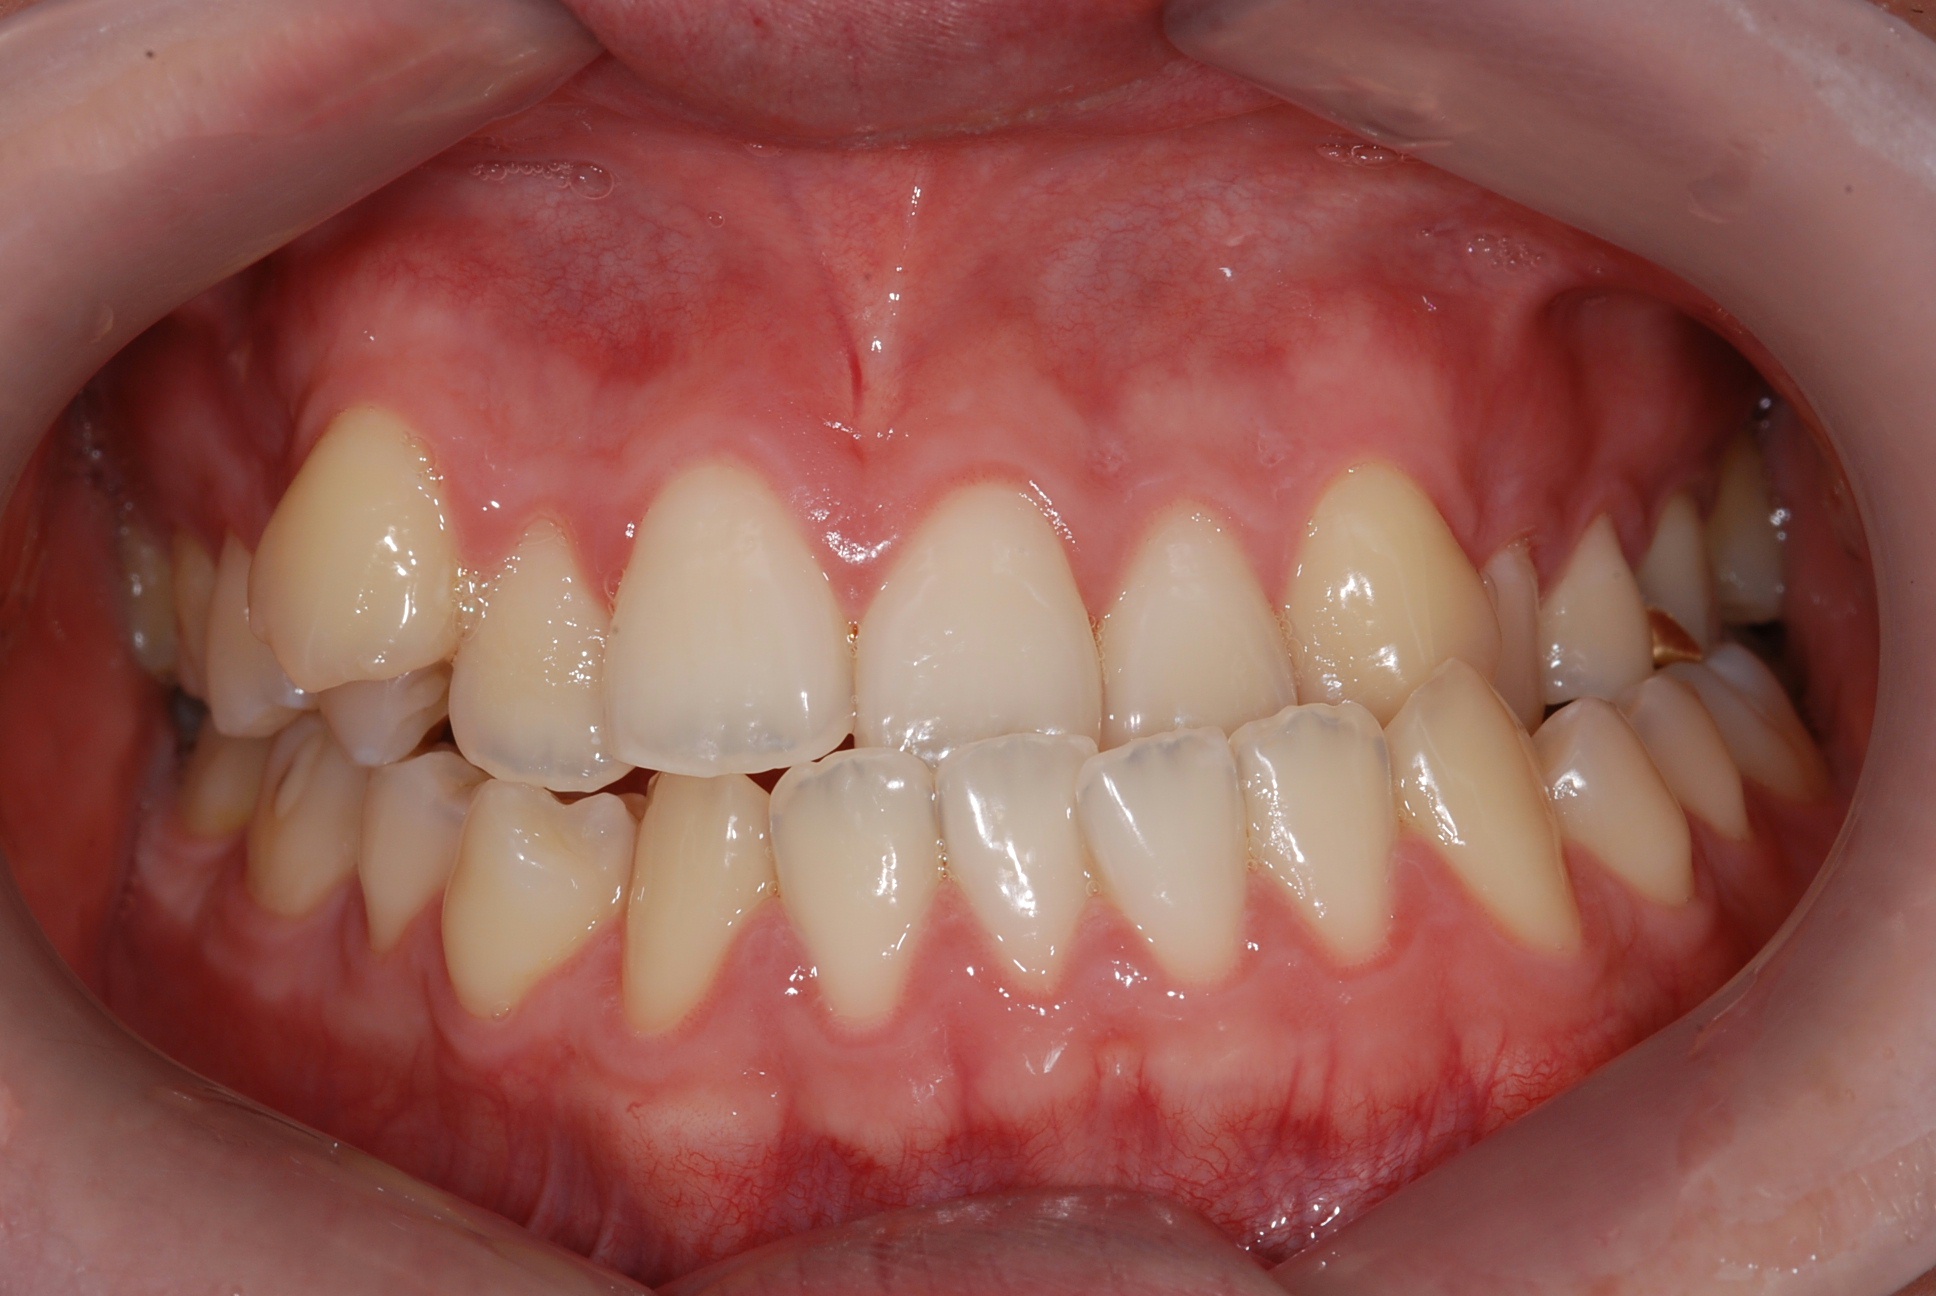

치료 전 사진입니다.